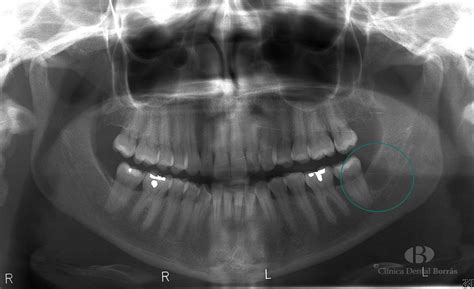

Quistes Maxilares

Los quistes son cavidades revestidas de epitelio que contienen un material líquido o semisólido en su interior. Los quistes son de carácter benigno, aunque en un porcentaje ínfimo pueden convertirse en malignos. En la mayoría de los casos son benignos, aun cuando en algunos casos pueden evolucionar y convertirse en cancerosos. En el 90% de los casos se forman sobre los incisivos superiores.

Las localizaciones más habituales de los quistes son la mandíbula y el maxilar superior, concretamente, sobre los incisivos centrales o paletas. Se trata de una bolita en el hueso de la mandíbula que puede ser de dos tipos en el 90% de los casos:

- Quiste periapical o radicular: Son las entidades más frecuentes. El epitelio procede de los restos epiteliales de Malassez o restos del proceso de odontogénesis. La causa puede ser una caries o una reacción defensiva frente a un proceso inflamatorio persistente. En el segundo caso, recibe el nombre de granuloma.

- Quiste dentígero o de erupción: Se genera en el proceso de erupción y formación del diente. Lo que ocurre es que se produce un cúmulo de líquido entre la corona y el epitelio del órgano del esmalte que conforma el folículo o bolsa donde se encuentra el diente en formación y progresa hacia la encía.